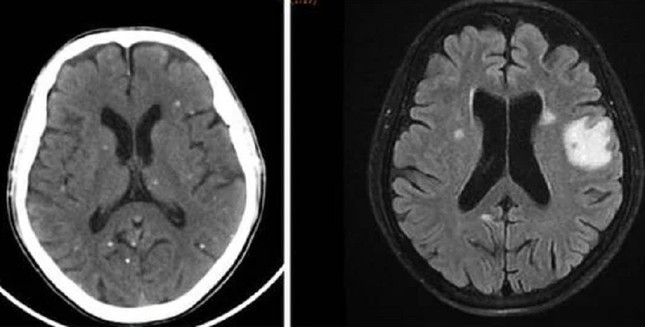

Nang sán dải ký sinh ở bán cầu não hai bên là nguyên nhân khiến người bệnh bị tổn thương não, biểu hiện như đột quỵ

TS.BS Trần Thanh Hùng, Phó khoa Nội Thần kinh Tổng quát, Bệnh viện Nhân Dân 115 cho biết, qua thăm khám và chẩn đoán hình ảnh ghi nhận, người bệnh có tổn thương não nhiều vị trí, phù não. Kết quả xét nghiệm huyết thanh học cho thấy, bệnh nhân dương tính với ấu trùng sán dải lợn (Cysticercus).

Trên kết quả X-quang và CT-Scan toàn thân, bác sĩ phát hiện bệnh nhân có vô số nang sán dải còn sống hoặc đã bị vôi hóa ở não, nhu mô phổi, trong da, cơ trên toàn bộ cơ thể. Qua điều tra dịch tễ, bác sĩ ghi nhận bệnh nhân có thói quen hay ăn gỏi thịt lợn tái sống và uống nước không đun sôi trong nhiều năm.

Ấu trùng nang sán dải lợn ký sinh khắp cơ thể người bệnh được phát hiện trên kết quả kiểm tra hình ảnh